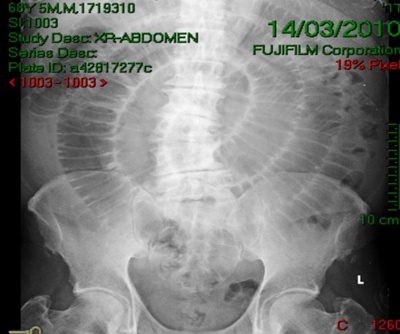

זו מבוססת על צילום בטן סקירה שבו ייראו:

- תמונה של חסימת מעי דינמית (תצלום 43.8)

- במקצת מהחולים ייראו גבולות האבן המסומנים על-ידי הגז במעי